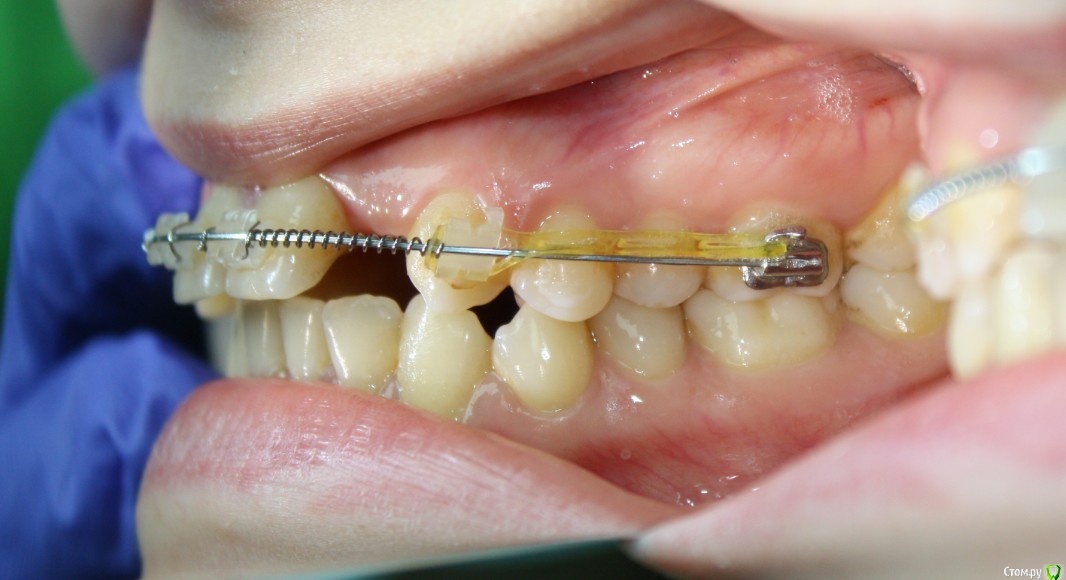

Здравствуйте коллеги! На консультацию обратилась пациентка, сейчас находится на ортодонтическом лечении. Предистория: три года назад обратилась к стоматологам с жалобой на неудовлетворительную эстетику фронтального отдела, вследствие врожденного отсутствия латеральных резцов. Ей было предложено ортодонтически создать место для боковых резцов, затем провести имплантацию и протезирование на имплантатах 12, 22.

Затем, с ее слов, идет длительный этап ортодонтии, почти 3 года, вследствие которого получили немного места для двоек, которого не достаточно для иплантации, так же центральные резцы ушли вперед, образовалась саггитальная щель.

Фото сегодня:post-461-0-94195200-1456407270_thumb.jpgpost-461-0-97652100-1456407271_thumb.jpgpost-461-0-40898500-1456407273_thumb.jpgpost-461-0-68973300-1456407274_thumb.jpgpost-461-0-88108800-1456407275_thumb.jpgpost-461-0-99061300-1456407276_thumb.jpgpost-461-0-92547500-1456407277_thumb.jpgpost-461-0-02811200-1456407279_thumb.jpgpost-461-0-05035300-1456407280_thumb.jpgpost-461-0-27197600-1456407281_thumb.jpg